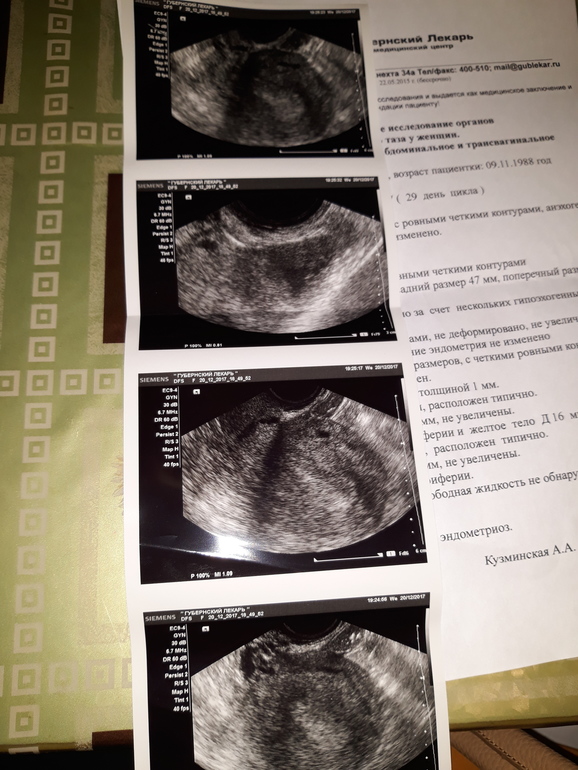

Ну вот и узи.

Сказала,что беременность еще очень рано смотреть.Но эндометрий пышный,овуляция была,желтое тело есть.Если сбоев не было,тесты слабоположительные,значит беременность есть.Через неделю приходите,уже будет видно.А так сдавайте хгч.Эндометриоз еще нашла...Хотя три месяца назад его и в помине не было.